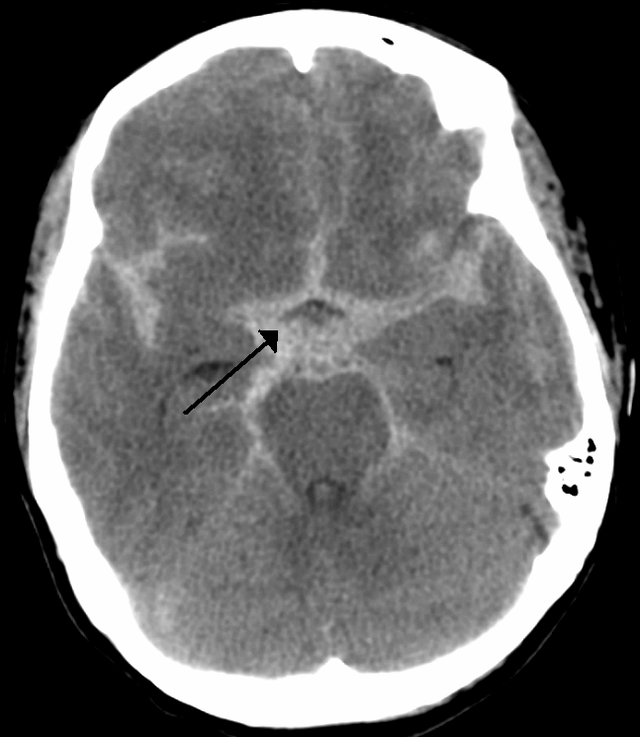

- Ventricular size: Look for dilatation, compression or asymmetry suggesting hydrocephalus, raised ICP or mass effect.

| Subarachnoid haemorrhage (SAH) | Hyperdensity in sulci, basal cisterns, or fissures. Diffuse SAH shows widespread cortical sulcal hyperdensity; localised SAH may be focal in a specific sulcus or cistern. |

| Cerebral venous thrombosis | May show “empty delta sign” with contrast (unenhanced thrombus centrally with enhancing sinus wall), venous infarcts, or haemorrhagic venous infarcts. |